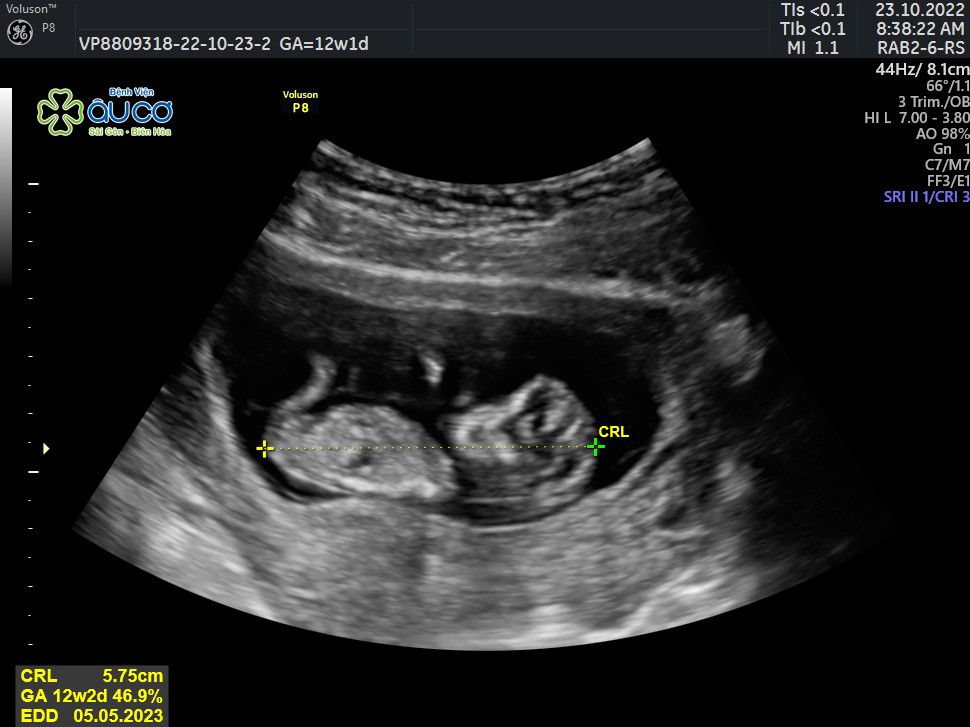

* Những hình ảnh siêu âm đáng yêu nhưng không kém phần nghịch ngợm của con qua các mốc thời gian:

![]() |

| 12 tuần 1 ngày |